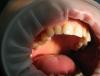

Уважаемые коллеги, ко мне пришла пациентка с жалобами на эстетику во фронтальной группе, слева.

Объективно:

1. транспозиция 2.3 и 2.2;

2. 2.2 дистопирован, кариозная полость на небной поверхности, подвижность в пределах физиологической;

3. скученность 1.2; 1.1; 2.1; 2.3; 2.2;

4. в боковых движениях: вправо- ведение клыковое, влево- ведение на 2.2.